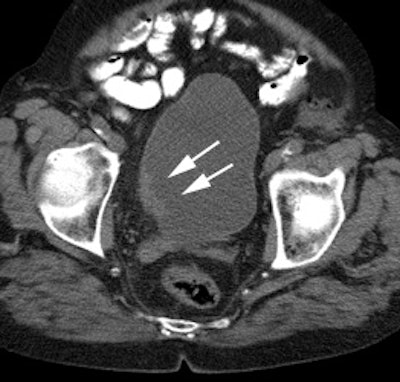

|

Bladder cancer: Dilute urinary activity in this patient's bladder allowed accurate detection of their bladder cancer (white arrows on CT, black arrows on PET scan). In general, urinary excretion of FDG limits evaluation of urinary tract malignancies, however, hydration and diuresis can improve diagnostic accuracy. |